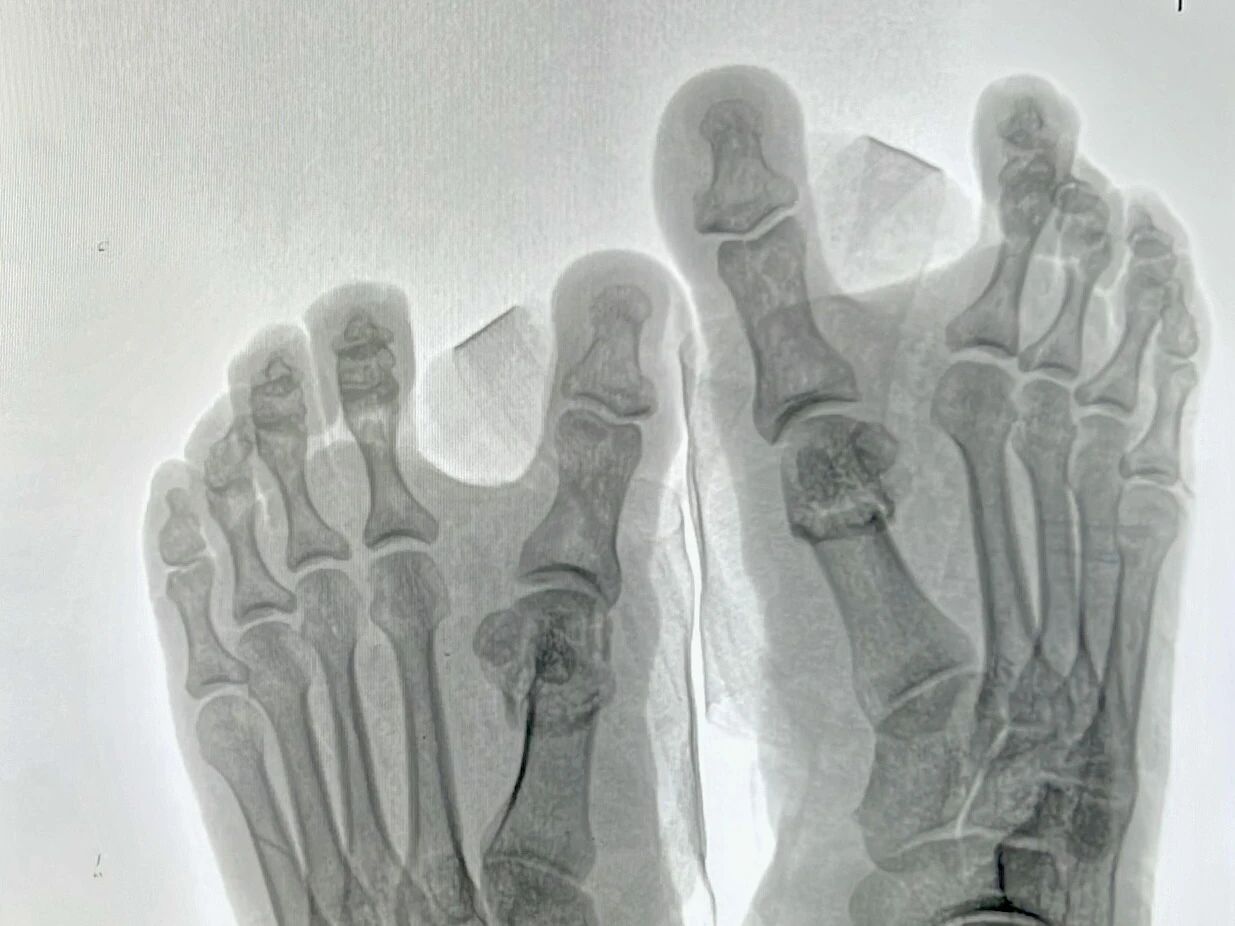

▲术后即刻行走

近日,周口人合医院迎来中国中医科学院广安门医院骨科徐颖鹏博士。作为国家级骨科大咖,徐博士此次专程为周口患者带来国际先进的微创诊疗方案,让群众在家门口即可享受顶级医疗技术。在当天的诊疗活动中,多名拇外翻患者成为首批受益者,徐博士采用局部麻醉,不到四分钟便完成单侧手术,创口仅如米粒大小,术后即可行走。 ▲徐颖鹏博士为多位患者行拇外翻微创手术 一位刚刚结束手术的患者惊喜地表示:“这十几年一直被脚变形和疼痛折磨,没想到在人合医院不到十分钟就彻底解决了!真是太神奇了!” ▲术前